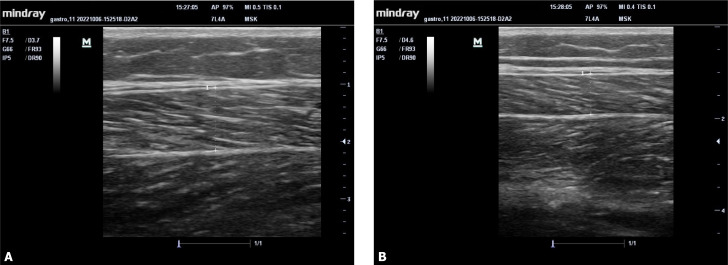

Methods: Twenty-two FMS patients and 18 asymptomatic control cases who applied to the physical medicine and rehabilitation outpatient clinic were included. The thickness of the gastrocnemius medialis/lateralis, trapezius, and upper arm muscle was evaluated with ultrasonography. Muscle strength was evaluated with hand grip strength, muscle performance with chair stand test (CST), walking performance with 10 m walking test, disease severity with Fibromyalgia Impact Questionnaire-Revised, pain severity with VAS, and kinesiophobia with TAMPA kinesiophobia scale.

Abstract Image